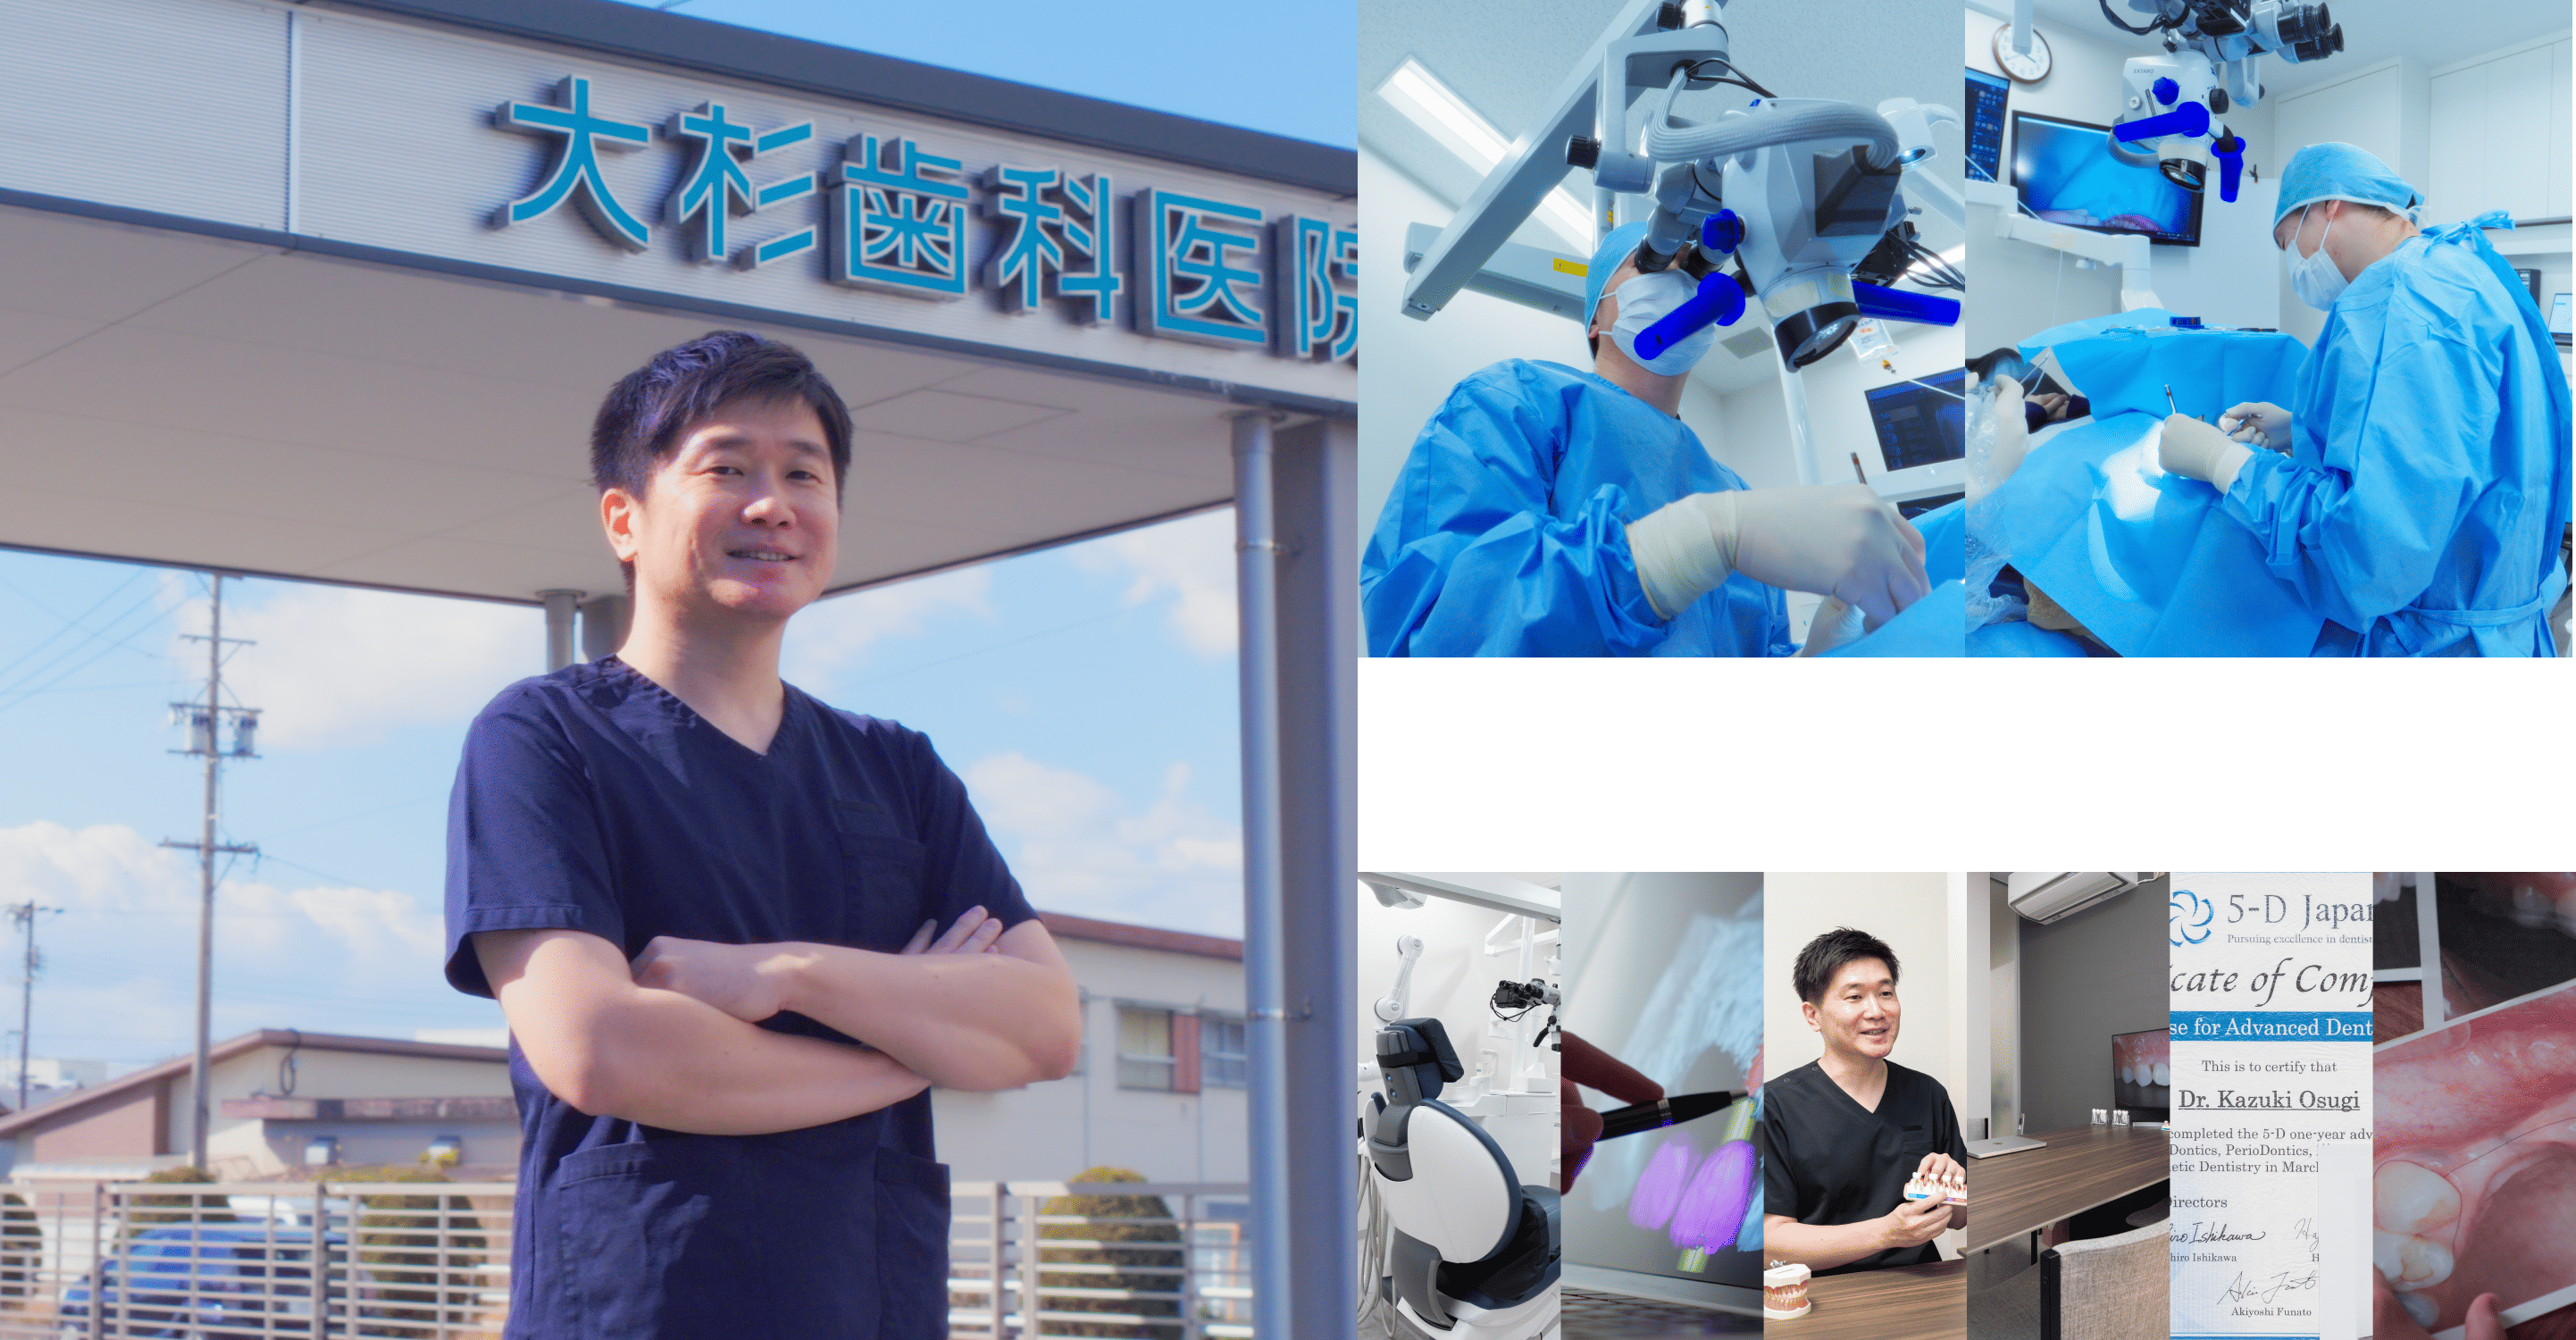

近年では、骨量が不足していてもインプラント治療を可能にする再生療法が進化しており、大杉歯科医院でもその技術を取り入れることで多くの患者さまに治療の選択肢を広げてきました。

大杉歯科医院では、難症例に多数対応してきた実績を活かし、「他では無理と言われた」ケースでもあきらめずに治療の可能性を模索しています。

大杉歯科医院では、これまで他院で「治療が難しい」とされた症例にも真摯に向き合い、再生療法や即時埋入といった先進技術を用いて新たな選択肢をご提示してきました。

患者さまの「もう一度しっかり噛めるようになりたい」「笑顔に自信を持ちたい」といった想いに寄り添い、最適な治療方法を対話と診断を通して一緒に導き出す――それが、当院の変わらぬ姿勢です。